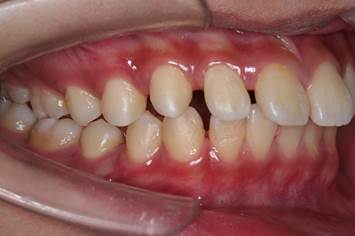

1.青少年综合矫治:包括乳牙期及替牙期早期治疗,口腔不良习惯的纠正,以及牙齿排列不齐、牙列拥挤或间隙、埋伏牙牵引、“地包天”或“龅牙”、上颌前突、下颌后缩、双颌前突、前牙开合及轻中度骨性错合畸形的系统治疗。

2.成人正畸治疗:骨性畸形的正畸掩饰治疗,露龈微笑矫治,牙周病患者正畸治疗,牙列修复前正畸治疗。

3.唇腭裂患者正畸治疗:包括严重错位牙的矫治,上颌骨横向及纵向发育不足的治疗,牙槽突裂植骨前的正畸治疗等。